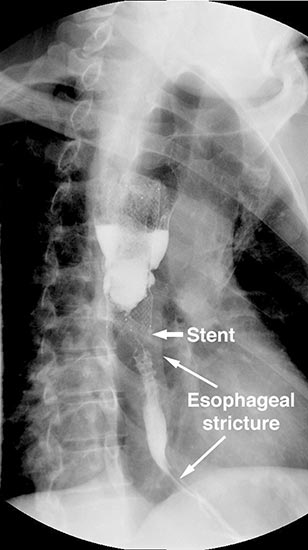

A 49 year old male presented to our institution with significant dysphagia and a 40 lb. weight loss secondary to a distal esophageal stricture. The patient had ingested lye 4 years previously and required partial gastrectomy, gastrojejunostomy, and partial colectomy at an outside institution at that time. His symptoms of dysphagia had progressively worsened despite repeated dilations and placement of an esophageal stent (Figure 1). Surgical reconstruction was therefore felt to be indicated. Preoperative computerized tomography angiogram did not clearly display the blood supply to the stomach, but did show that the colonic vasculature was adequate for use as a conduit if needed.

The abdomen was temporarily closed, and the patient was placed in left lateral decubitus position. A right posterolateral thoracotomy was made in the sixth intercostal space. After mobilization of the esophagus, it was divided one centimeter distal to the azygous vein, and the stent in the proximal esophagus was removed. After the stent was removed an esophagoscopy revealed normal esophageal mucosa and no injury or stricture of the proximal esophagus.